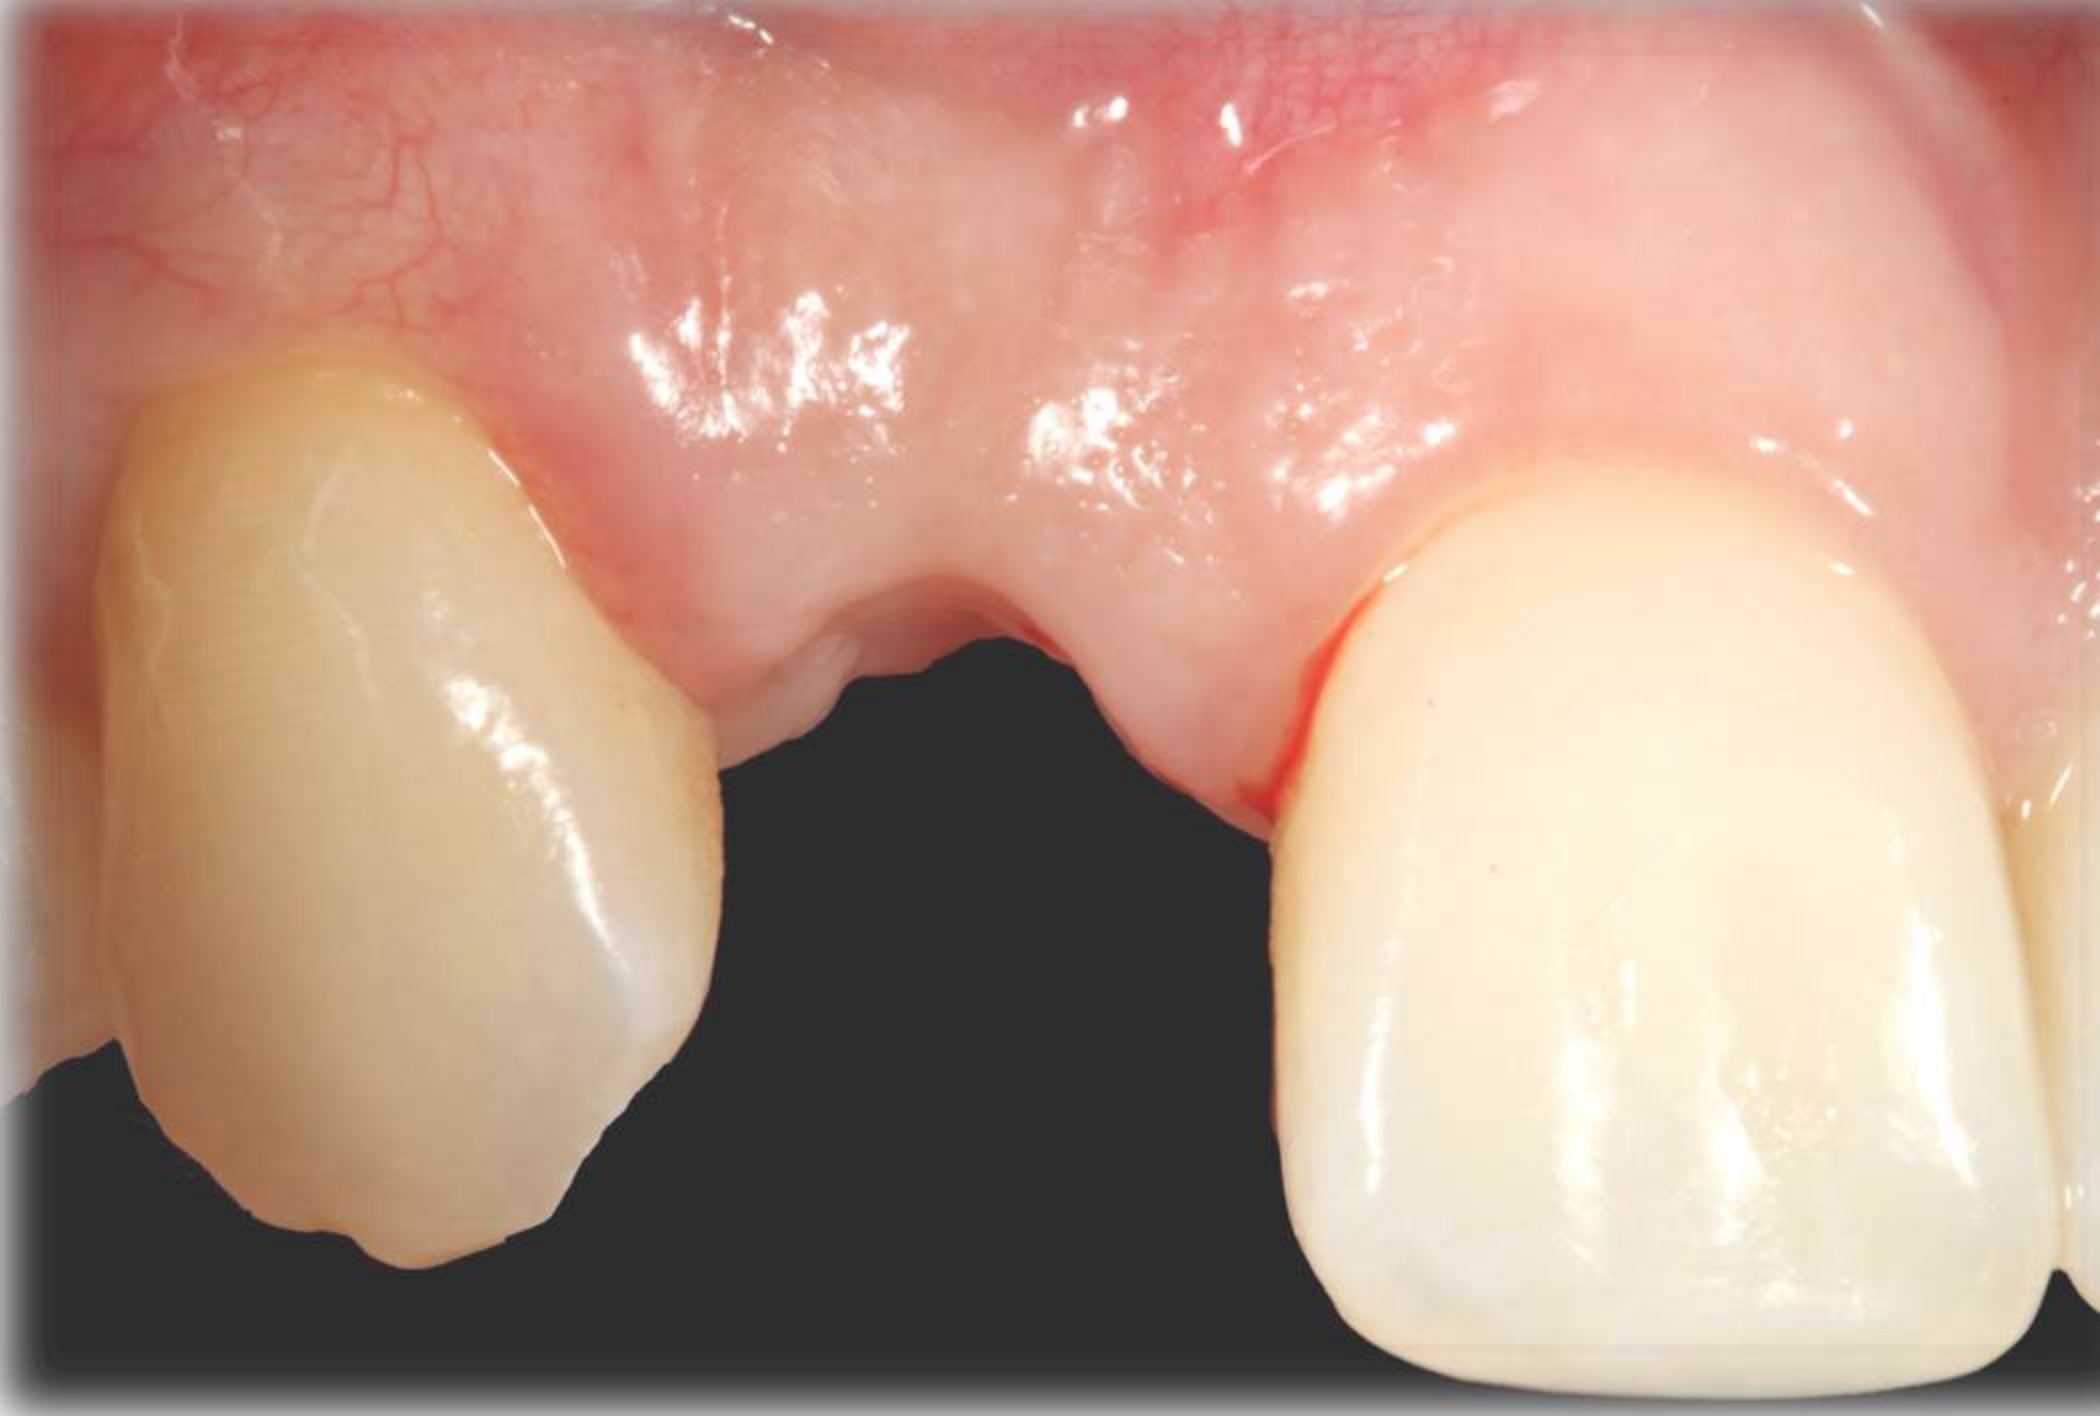

Fig 18. The final restoration after 4 months.

Figure 18

There are numerous scenarios when a papilla-sparing incision can be advantageously used, including implant placement, the reconstruction of soft tissue and bone, or both. Figure 10 through Figure 18 and Figure 19 through Figure 25 illustrate how papillae-sparing incisions can be used to restore form and function using a nonsubmerged implant protocol. (Surgeries were performed by DT.)